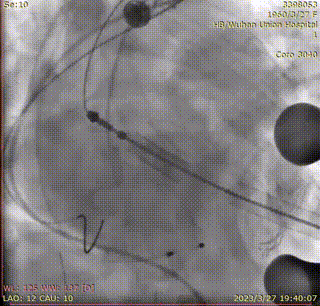

猪尾放置于无冠窦行根部造影,通过垫患者左肩、最终左前斜12°,实现三窦切线位:

穿刺心尖,跨瓣。定位件进入窦部,造影确认:

将瓣膜降至合适平面,造影: